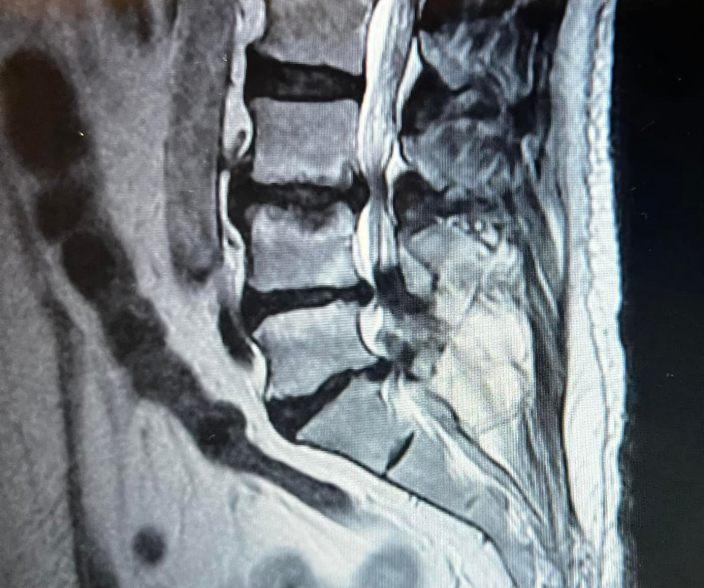

Cirugía endoscópica para hernias discales

Las hernias discales o de disco son bastante comunes y puede incapacitar gravemente al paciente, trayéndole consigo dolor crónico y disminucióndelamovilidad.

No obstante y a pesar de que su único tratamiento definitivoeslacirugíaparareparareldañoeneldisco intervertebral problemático, han surgido nuevas y mejores maneras de abordarlo quirúrgicamente, con mínimas consecuencias como con la cirugía endoscópica.

¿Qué es una cirugía endoscópica para hernias discales?

Esta técnica mínimamente invasiva constituye la mejor alternativa a la cirugía tradicional de hernia de disco, conocida como microdiscectomía, en la que es necesariorealizargrandesincisiones.

La principal ventaja de la cirugía endoscópica para la columna es que se reduce al máximo la manipulación de los delicados tejidos de la espalda y por ende, el dolor posterior a la cirugía y los riesgos asociados(comosangradosoinfecciones).

De esta manera, el paciente con hernia discal puede sentir confianza de que su problema será solventado rápidamente y solo usando anestesia local, con lo que podrá regresar a casa en poco tiempo a continuar la recuperación y lo mejor, la mejoría del dolor

¿Por qué ocurren las hernias de disco y en que casos serecomiendalacirugíaendoscópica?

Los discos intervertebrales son una especie almohadillas gruesas de cartílago que separan una vértebra de otra, permitiendo la movilidad de la columna y amortiguando los cambios de presión mientras caminamos, corremos o simplemente estamos sentados Sin embargo, en ocasiones el tejido que compone el anillo fibroso (la parte exterior de cada disco intervertebral) puede degenerarse y

hacerse frágil. Si ocurre un movimiento brusco, dicho anillo se rompe y expone parte del contenido pulposo (la parte interna del disco similar a una gelatina), desplazandose hacia el canal medular o las raíces nerviosas Esto es lo que produce dolor y puede afectarlafunciónnerviosa(movilidadysensibilidad).

El abordaje endoscópico de la cirugía de discos ha mostrado excelentes resultados en los siguientes tiposdehernias:

• Herniadiscaldelforamen.

• Hernia discal periférica al foramen (o extraforaminal,unadelasmásfrecuentes).

• Herniadiscalposteriorolateral.

No solo en las hernias discales ha sido útil esta técnica quirúrgica sino también en otros problemas de columna como la estenosis de canal medular, una patologíaenlaqueseestrechaelconductocentralde la médula espinal, ocasionando compresión, dolor crónico, pérdida de sensibilidad y de movilidad articular

Si la hernia discal se acompaña de procesos calcificados o espondilolistesis (menos frecuente), la cirugía de columna probablemente deba ser abierta oconvencional.

¿Cómo es la cirugía endoscópica para tratar hernias discales?

Serealizaconunpardepequeñasincisiones(de5a8 mm)enlapieldelaespalda,alaalturadelproblema. Allí se insertan una pequeña cánula con una cámara en su extremo (para visualizar las estructuras internas) y los instrumentos quirúrgicos. A través de ellos,elcirujanoevaluarálamagnituddelproblemay reparará el defecto (es decir, extraerá parte del tejido que está comprimiendo la medula y cerrará la aberturadelanillofibroso).

Alfinalizar,elcirujanocierraconsuturalaspequeñas incisiones en la piel y el paciente puede seguir descansando.